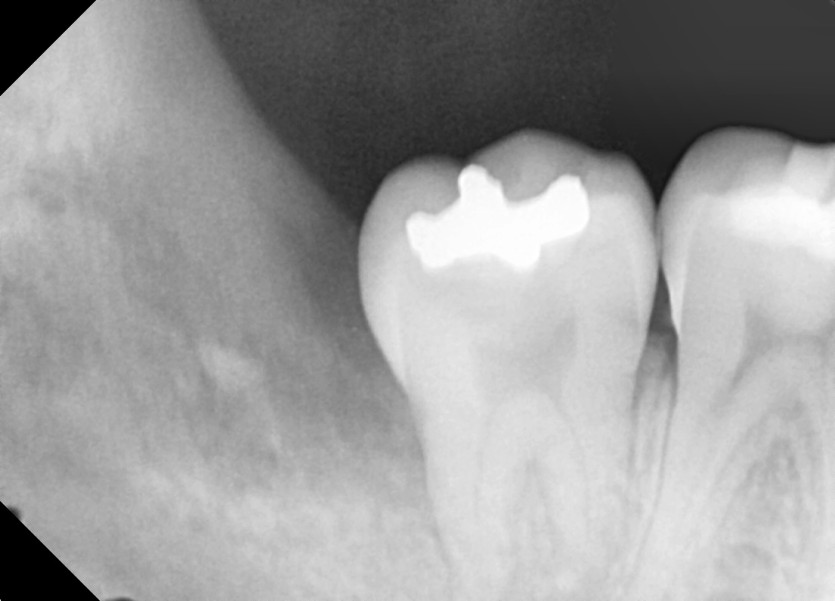

#38,48 사랑니 발치

구강 외과 전문의가 당일 발치했습니다.